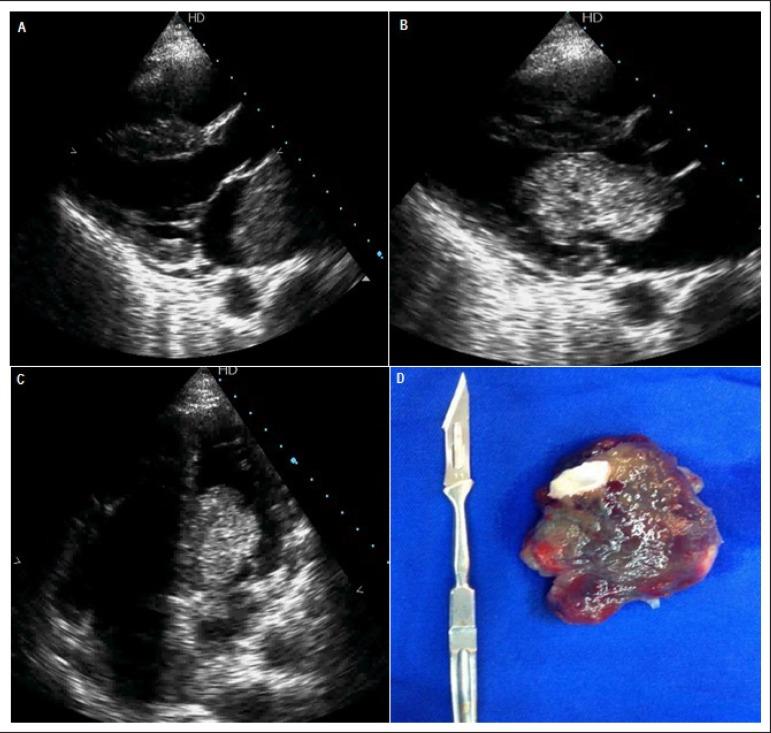

Patient with Atrial Myxoma and Signs of Obstruction of the Left Ventricular Outflow Tract.